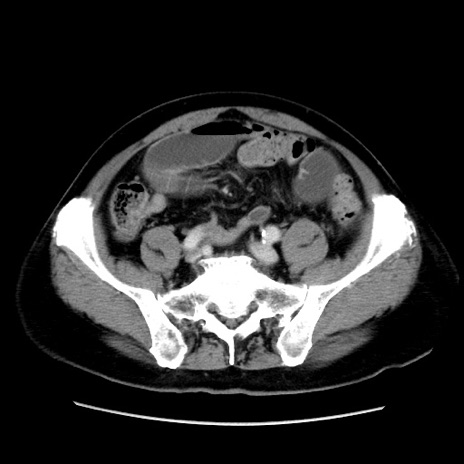

症例16(横断像)

【症例】 70歳代男性

【主訴】 腹痛、嘔吐

【現病歴】 約1ヶ月前より間欠的に腹痛と嘔吐あり、当院消化器内科を受診したところCTで多発する肝臓のLDAを指摘され、精査中であった。以降は消化器症状は安定していたが、2日前より嘔気と腹痛があり、同日より排便・排ガスが消失した。改善認めず、 本日、救急外来を受診した。

【既往歴】 大腸ポリープ切除後。

【身体所見】意識清明・会話良好、BT 36.3℃、BP 127/80mmHg、 P 80bpm、腹部:膨満あり、平坦・軟、上腹部正中および下腹部正中に圧痛あり、反跳痛なし、筋性防御なし。

【データ】WBC 7200、CRP 0.77